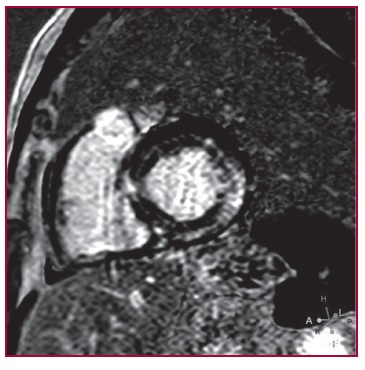

Amiloidosis senil cardíaca: patrón atípico de realce por resonancia magnética y utilidad de la gammagrafía/SPECT

IMÁGENES EN CARDIOLOGÍA